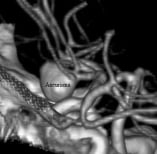

Angiografia projeção frontal de mulher de 48 anos portadora de doença renal policística. O círculo mostra o aneurisma cerebral.

Angiografia perfil mostrando 2 aneurismas: um da artéria comunicante anterior (círculo) e outro da artéria comunicante posterior (seta).

Projeção frontal da angiotomografia 3D mostrando o volumoso aneurisma.

Projeção perfil da angiotomografia 3D.

Angiotomografia reconstrução 3D mostrando a clipagem de ambos os aneurismas (clipes em roxo).